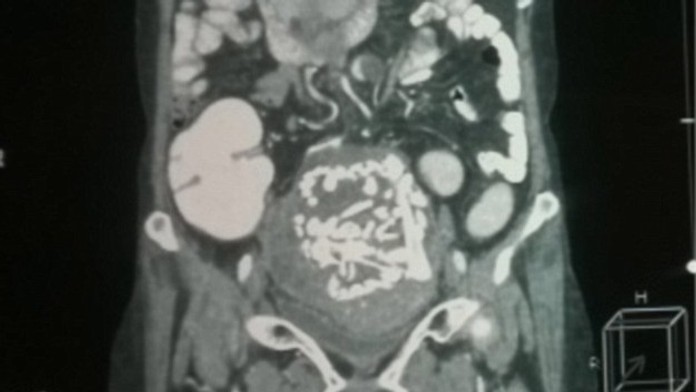

V mestskej nemocnici v Indii mal tím lekárov naozaj unikátny prípad. Obyvateľku Indie, Thakre (60) trápili už dlhšie bolesti brucha. Keď však zašla k lekárovi, nikto neveril vlastným očiam. V jej brušnej dutine našli 36-rokov starú kostru dieťaťa.

Ako sa tam dostala?Kantabai Thakre, z Indie otehotnela, keď mala 24 rokov. Písal sa rok 1978 a lekári jej vtedy oznámili, že jej dieťa má len malú šancu na prežitie. Rástlo totiž mimo maternice. Vydesená matka však pred operáciou utiekla. O 37 rokov neskôr však Kantabai zažívala nesmierne bolesti brucha.

Kantabai Gunvant Thakre našli po ultrazvuku v jej brušnej dutine. Zprvu si mysleli, že je to rakovina. Po opakovaných vyšetreniach ich však výsledok vyviedol z miery.

"Po tom, čo pacient podstúpil vyšetrenie magnetickou rezonanciou, lekári usúdili, že ide o kostru dieťata," hovorí Dr. Murtaza Akhtar, vedúci chirurgie v Indickej nemocnici.

"Požiadali sme o podrobnú anamnézu. Samotná pacientka nám neskôr povedal, že v roku 1978 bola tehotná a mala nejaké komplikácie," povedal Dr BS Geda, ktorý viedol tím lekárov.

Operáciu lekári vykonali 14. augusta, trvala štyri hodiny. Podľa lekárov sa pacientka rýchlo zotavuje.